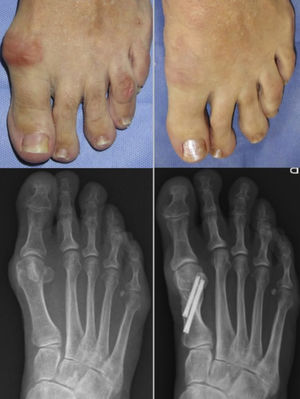

Se permite también deambulación con zapato postoperatorio con carga inmediata. Se indican curas semanales y se retira la aguja de Kirschner en consultorio en la tercera semana postoperatoria (figs. 3 y 4).

ResultadosSe incluyeron para el estudio 38 pacientes operados de hallux valgus mediante técnica en chevron percutánea con liberación del tendón aductor (grupo Chevron) y 38 pacientes con técnica de Bosch (grupo Bosch), entre enero de 2016 y enero de 2017. Los datos demográficos se muestran en la tabla 1.

El tiempo medio de consolidación fue para el grupo de osteotomía en chevron de 13,36 semanas (SD 3,03), y de para osteotomía de Bosch 13,60 semanas (SD 2,43), no siendo significativa la diferencia entre ambos grupos (p > 0,10).

En la escala AOFAS se demostró un aumento de los valores promedio de 58,88 (SD 8,80) a 97,15 (SD 4,81) a los 12 meses (p < 0,0001) para la osteotomía en chevron percutánea, y de 59,19 (SD 10,46) a 98,72 (SD 2,87) (p < 0,0001) en la osteotomía de Bosch.

En el análisis comparativo entre ambas técnicas, no se demostraron diferencias significativas en cuanto a correcciones angulares radiológicas ni en la escala AOFAS.